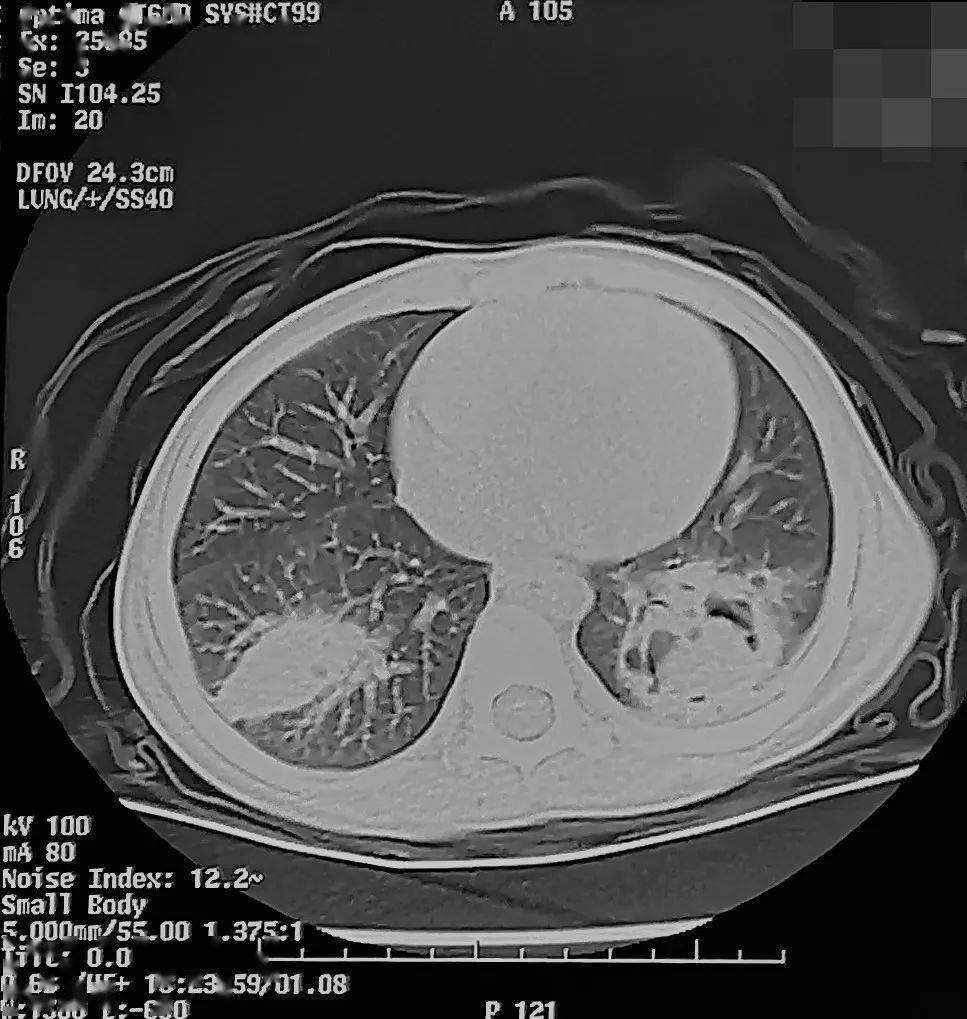

儿童怀疑支原体肺炎,为何需要查胸片,乃至胸ct